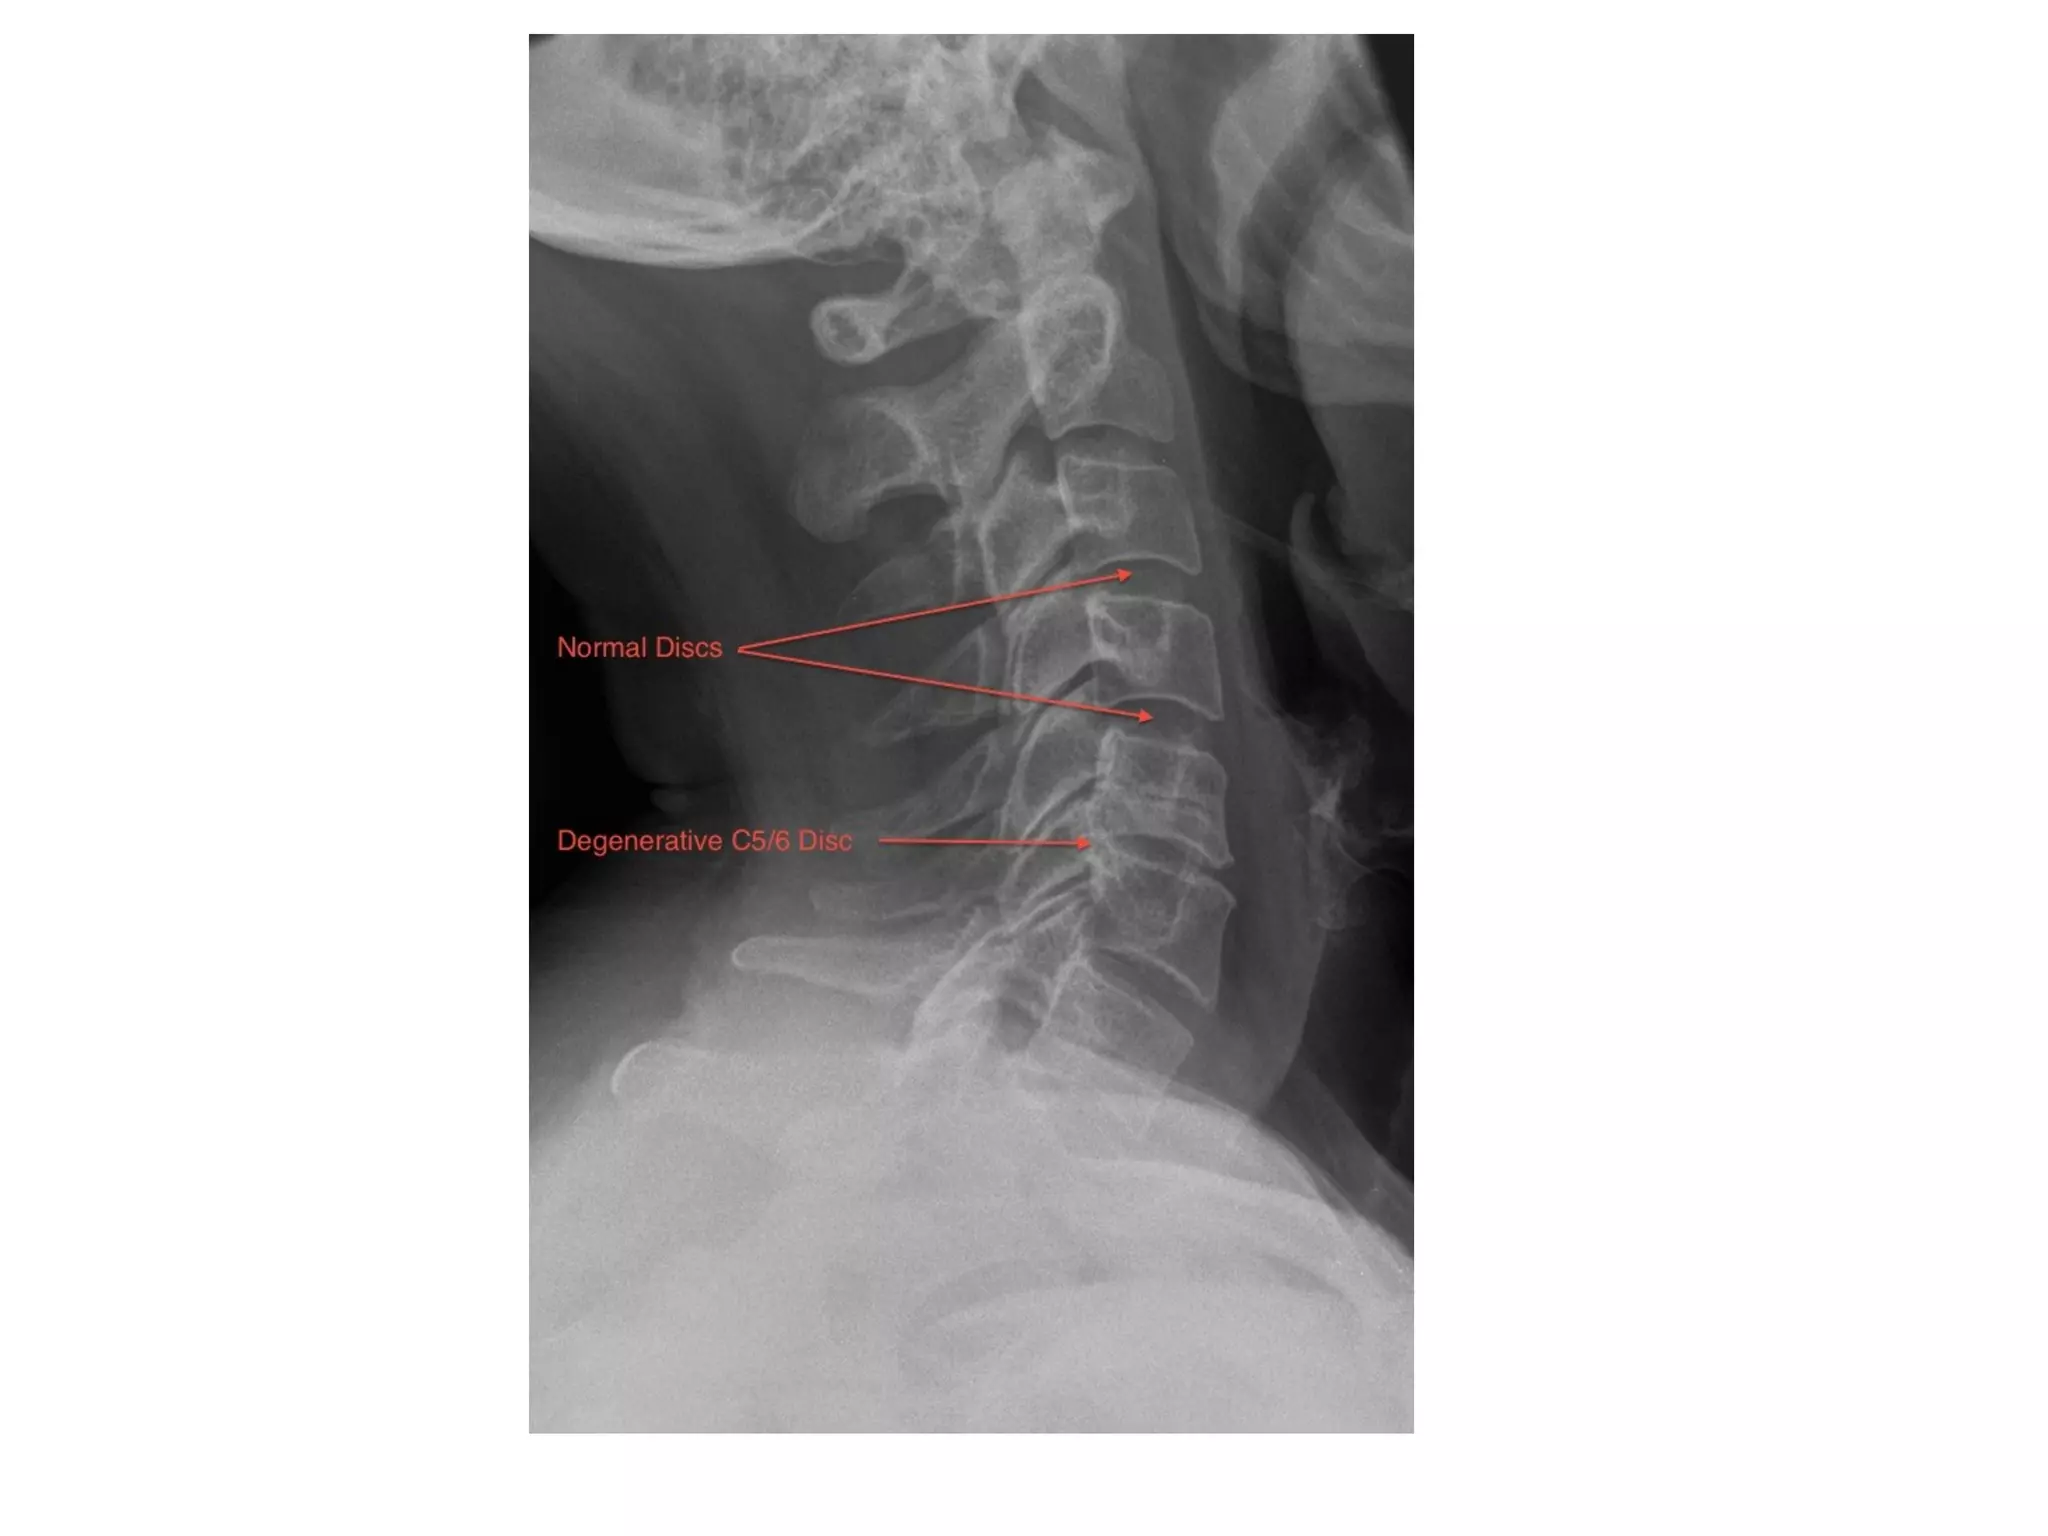

1-Plain Radiography :

-Disk space narrowing

-Vacuum phenomenon in disk space (gas in the

intervertebral disc) , pathognomonic for

degenerative disease

-Endplate osteophytes and sclerosis